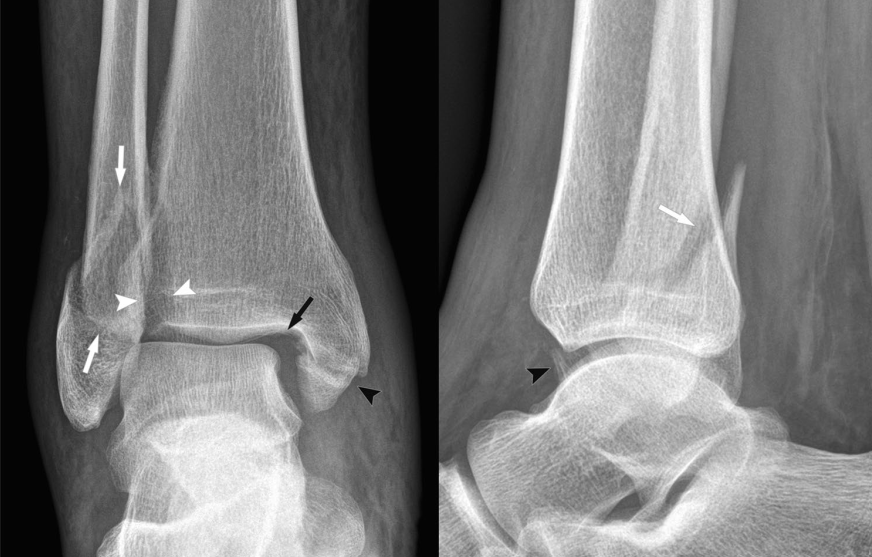

然而,在临床实际应用中,常规X线摄片仅能明确骨折情况,对下胫腓韧带损伤、外侧韧带、内侧三角韧带的损伤不能直接判断,需结合损伤机制推断,为避免漏诊韧带损伤,有学者提出了“损伤环”理念,旨在通过“环”的损伤顺序,推断合并的韧带损伤。

1. 旋后外旋损伤

对踝关节损伤机制的判断,首先观察外踝骨折线形态。对前低后高型外踝骨折线,提示旋前外旋损伤。依据“损伤环”理念,下胫腓前韧带、外踝、下胫腓后韧带、内踝组成的环依次损伤,分别标为“1-4”,后方损伤提示必定存在前结构的损伤。